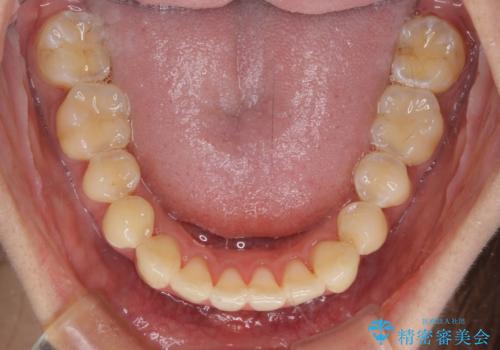

八重歯の再矯正 インビザラインでストレスなく矯正治療

- 学生の頃に矯正治療を行ったものの、保定を怠けてしまったことによる後戻りを気にして来院された患者様です。

根管治療が必要な歯があったため、矯正治療前に根管治療を行い、その後はインビザラインにより矯正治療を行うこととしました。

下顎の八重歯が上顎歯列に収まる過程で咬みにくさがありましたが、最終的には、咬み合わせも安定し、きれいに歯列を整えることができました。